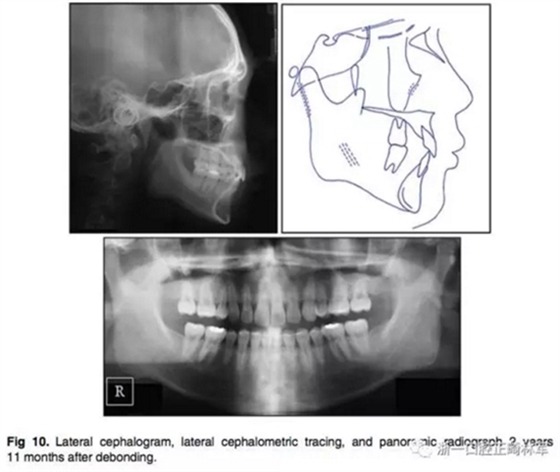

3.在2年11個(gè)月后,患者回來復(fù)診,他的面部形態(tài)仍然可以接受,但是他的唇部厚度顯著增加,結(jié)果,他的唇部已經(jīng)變得略微突出(Fig 9、Fig10)。他的咬合仍然穩(wěn)定,但他的咬合力略有增加。切牙區(qū)出現(xiàn)了間隙。

4.頭顱測量疊加顯示有一定的下頜頜骨生長。矢狀面骨關(guān)系穩(wěn)定(ANB由4.4為4.1°),下頜平面逆時(shí)針旋轉(zhuǎn)(Fig 11)。